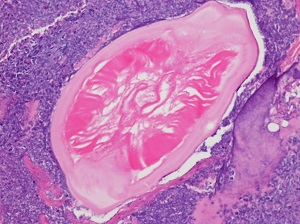

A 60-year-old non-smoking male patient presented to his primary care physician with a chronic cough and shortness of breath. He reported no recent travel outside of the Southern United States. A CT scan revealed focal consolidation and cavitation. Later, a lung biopsy was performed on a lesion that revealed possible parasitic forms on histopathological examination. Images A—C show the objects of interest in the hematoxylin and eosin (H&E) stained slides; the size of each object was approximately 200 µm in diameter. What is your diagnosis? Based on what criteria?

Figure A